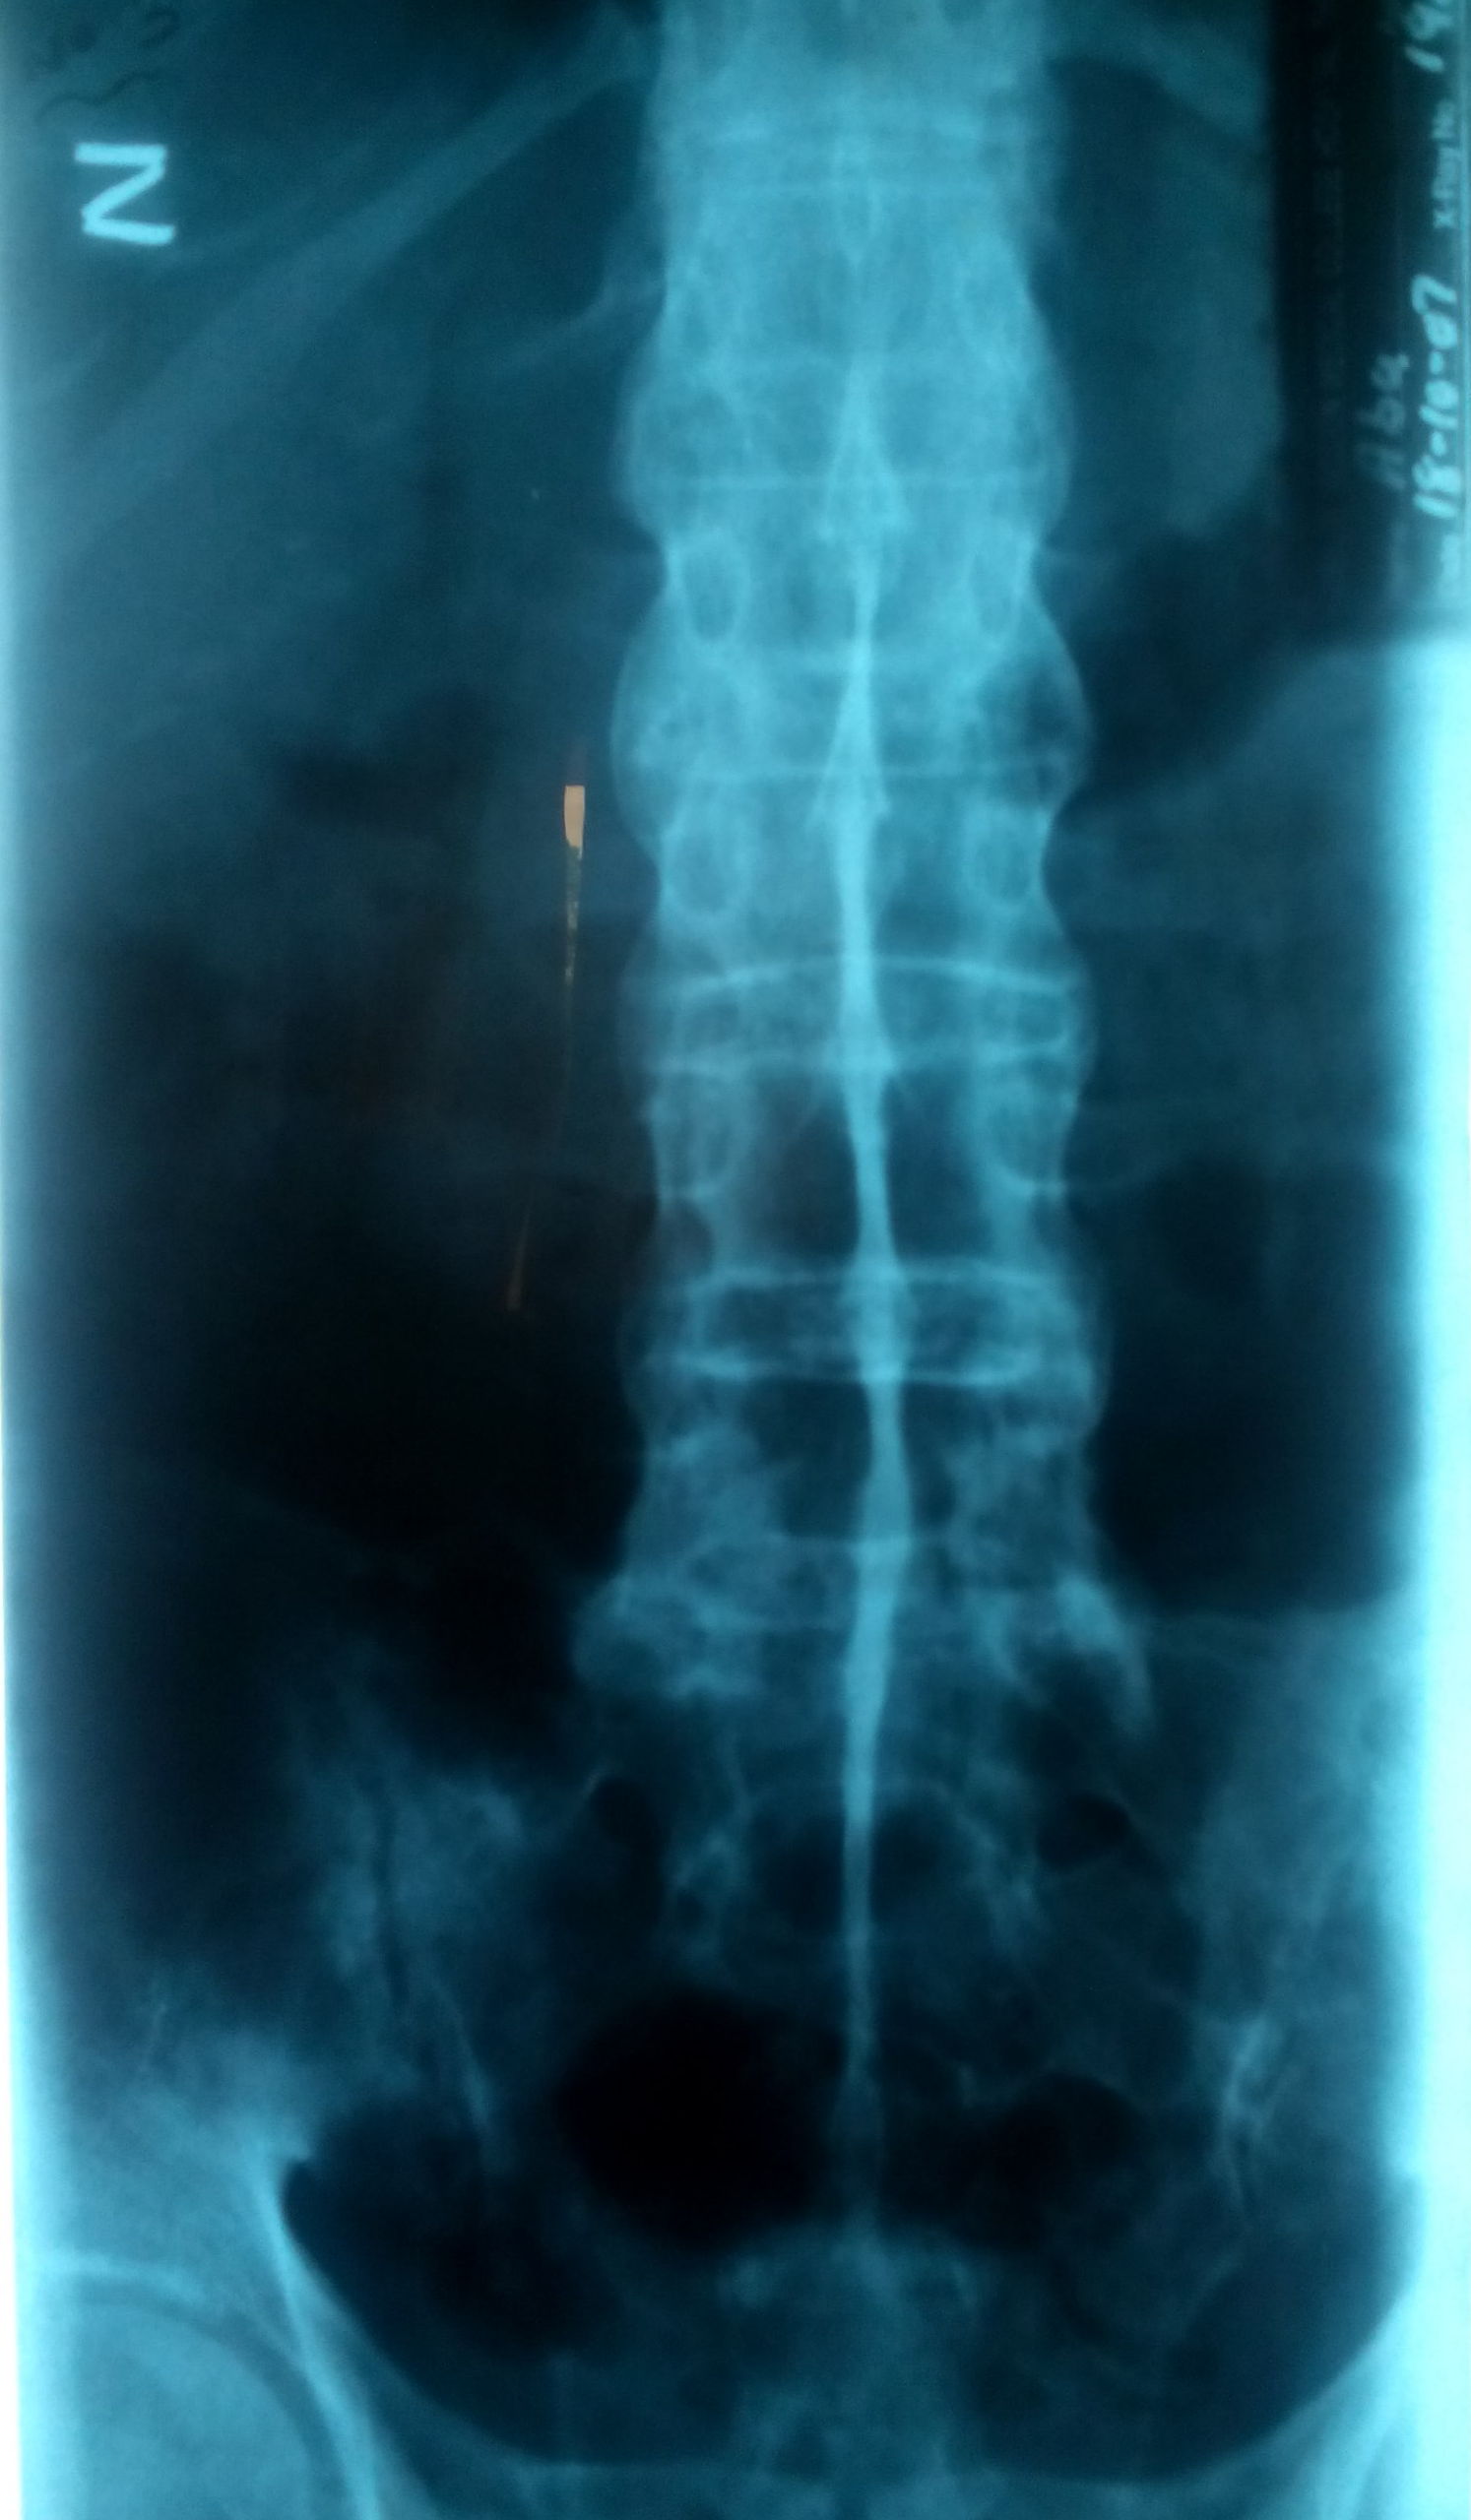

Lumbar Spine A.P view of elderly patient

A S dagger sign 2